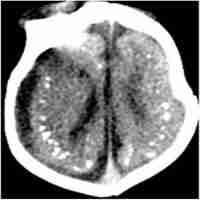

| Abstract | Now that scientific consensus that Zika virus is a cause of microcephaly and GBS has been reached, it is time to act. The virus is spreading uncontrollably across the world: since 2015, a total of 70 countries or territories have reported vector-borne Zika virus transmission, and at-risk countries need to be prepared to manage patients with neurological disorders. However, effective and joint strategies between all stakeholders worldwide focusing on prevention are most urgently required. About the Authors |

| Subject Keyword | Guillain-Barre Syndrome Microcephaly Patients Zika Virus Infection nervous system disorder |